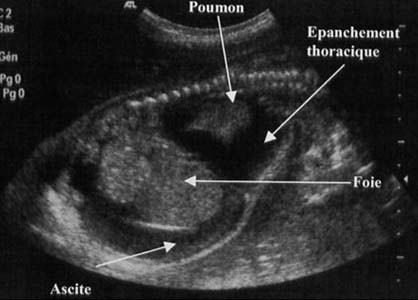

Eversion du diaphragme - hypoplasie du poumon sain